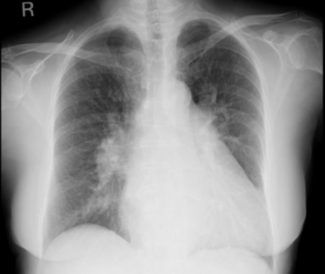

A 50-year-old man with a medical history of active smoking and diagnosed with type 2 diabetes mellitus was admitted to the ED complaining of sudden acute chest and left groin pain lasting 1 hour.